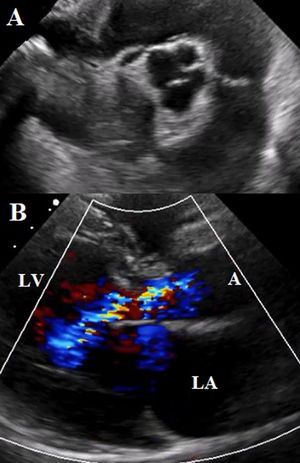

The transthoracic echocardiogram reported a dilated left ventricle with no motion abnormalities. LVEF of 51%. Quadricuspid aortic valve with sclerosis of its cusps, adequate opening, closure defect with a central jet that covers more than 2/3 of the left ventricular outflow tract. Vena contracta of 7mm. Aortic valve area of 2.4cm2, regurgitant volume of 79ml, indicating severe aortic regurgitation (Fig. 2).